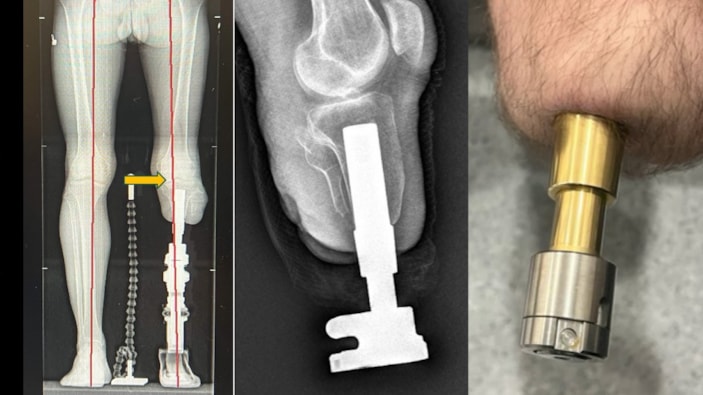

Kemiğe yerleştirilen implantlarla daha doğal ve konforlu bir yürüyüş sunan bu yöntem Türkiye’de de uygulanıyor.

Bu yöntemde, kemiğe yerleştirilen implant sayesinde yük doğrudan kemiğe aktarıldığından, çok daha doğal ve konforlu bir yürüyüş mümkün oluyor.

Osseointegrasyon protezlerinin yapıldığı uzuvlar hakkında da bilgi veren Prof. Dr. Kara, yöntemin uyluk, kaval kemiği, dizüstü ve dizaltı gibi bölgelerin yanı sıra üst kol amputasyonlarında da başarıyla uygulandığını aktardı.